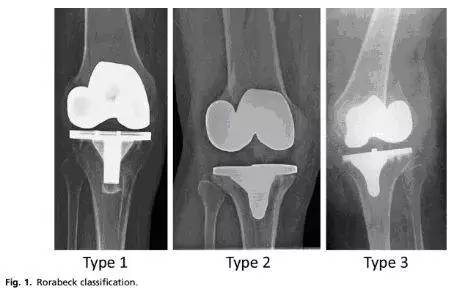

理清tka 术后股骨侧假体周围骨折的手术方法 北京卓然公益基金会 Powered By Pageadmin Cms

精彩幻灯 全膝关节置换术后的并发症

骨哥理论课堂 一文理清tka 术后股骨侧假体周围骨折的手术方法